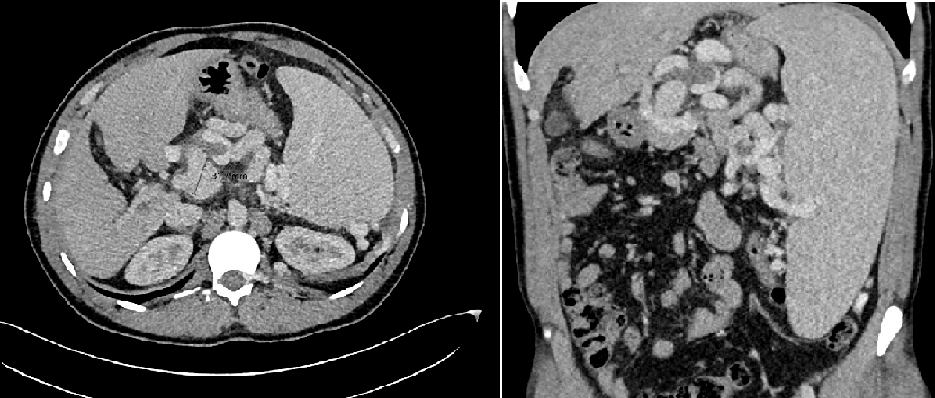

Ziele: Erfolgreiche endosonographisch-gesteuerte Coil- und Histoacrylbehandlung von Varizen an der Hepatikojejunostomie nach Pankreaskopfresektion nach Traverso zur Blutungsprophylaxe

Methodik: Externe Vorstellung des Patienten mit Meläna und vorliegen einer komplexen anatomischen Ausgangssituation bei Zustand nach pyloruserhaltender Pankreaskopfresektion mit Teilresektion der Pfortader aufgrund chronischer Pankreatitis. Zusätzlich besteht eine Pfortaderthrombose mit konsekutivem portalen Hypertonus. In der extern durchgeführten Gastroskopie zeigte sich frisches Blut in den Dünndarmschlingen sowie Ösophagusvarizen Grad III. In der durchgeführten Computertromographie (CT) konnte keine aktive Blutung nachgewiesen werden, jedoch bestanden ausgeprägte portosystemische Kollateralen. Es erfolgte die Übernahme in die Universitätsmedizin Göttingen. Hier erfolgte eine transhepatische Stentimplantation der Vena portae nach erfolgreicher transhepatischer Rekanalisation. Im weiteren Verlauf zeigte sich jedoch in der CT-Untersuchung eine In-Stent-Thrombose, woraufhin eine erneute, jedoch frustrane Rekanalisationsmaßnahme durchgeführt wurde. Entscheidung zur endoskopischen Intervention.

Ergebnis: Die Hepatikojejunostomie konnte erfolgreich endoskopisch dargestellt werden. Es zeigten sich mehrere ausgeprägte Gefäßkonvolute im Sinne von Varizen. Nach gezielter Punktion einer Varize erfolgte die Applikation von drei mit Faser versehenen Coils (je 7 mm). Zusätzlich wurde eine Portion Histoacryl injiziert. Im Anschluss wurde eine weitere Varize punktiert und mit zwei Coils (8 mm, ohne Faser) sowie zwei Portionen Histoacryl versorgt. Endosonographisch zeigte sich im Farbdoppler ein sehr gutes Akutergebnis. Endoskopisch traten keine akuten Komplikationen auf.

Abbilung 1: Endoskopisches Bild der Ösophagusvarizen (A) und der Varizen im Bereich der Hepatikojejunostomie (B)

Abbildung 3: (A) Preinterventionelle transkutane Sonographie mit Darstellung der Varizen, (B) Postinterventionelle transkutane Sonographie